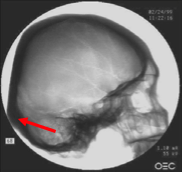

Step One: X-Rays

Lloyd first arranged for both skulls to be x-rayed. This revealed that the portion of the upper jaw of the deformed skull had several impacted teeth (showing up at the 5 dark globs in the x-ray image [above right] and suggested that the skull belonged to an individual who died at about 5 or 6 years old.

The next obvious anomoly was the frontal sinus regions. The human skull [abov: left and center] showed typical frontal sinuses between the eye sockets. The deformed skull had no trace of frontal sinuses, not even vestigial bumps indicating where its

sinuses might have attempted to grow. This is considered extremely unusual. Considered vital for screening dust and particles from reaching the lungs, only about 5% of humans are born without frontal sinuses.